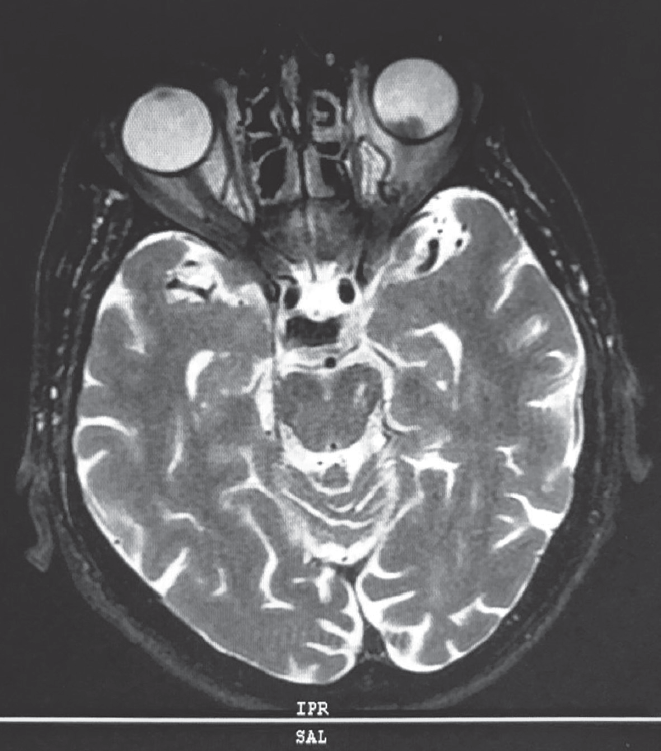

Ophthalmological examination data included examination of the visual acuity of the right eye of 0.8, which was incorrigible and that of the left eye was hand motion. The tonometry result was 18/17 mmHg. Biomicroscopy revealed no abnormalities in the anterior segment of both eyes. Particular attention was paid to the search for Lisch nodules in the iris, which were absent. At ophthalmoscopy, no focal pathologic change was detected in the right eye, while there was a protruding multinodular pink–orange neoplasm in the optic nerve head of the left eye, with clear boundaries, at the base of which, a retinal detachment was visualized in the lower fundus segments (Fig. 2). At the B-scan ultrasound examination, the optic nerve head had a protruding fungiform neoplasm (with height of up to 6.7 mm and diameter of up to 13.0 mm), medium echogenicity, and inhomogeneous density, at the base of which, retinal detachment was observed in the lower fundus segments (Fig. 3). Magnetic resonance imaging of the orbits also confirmed the presence of left eye neoplasm (Fig. 4).

Fig. 4. MRI of orbits. Intaocular tumor over the optic nerve

Рис. 4. Магнитно-резонансная томография орбит. Видна внутриглазная опухоль в проекции зрительного нерва